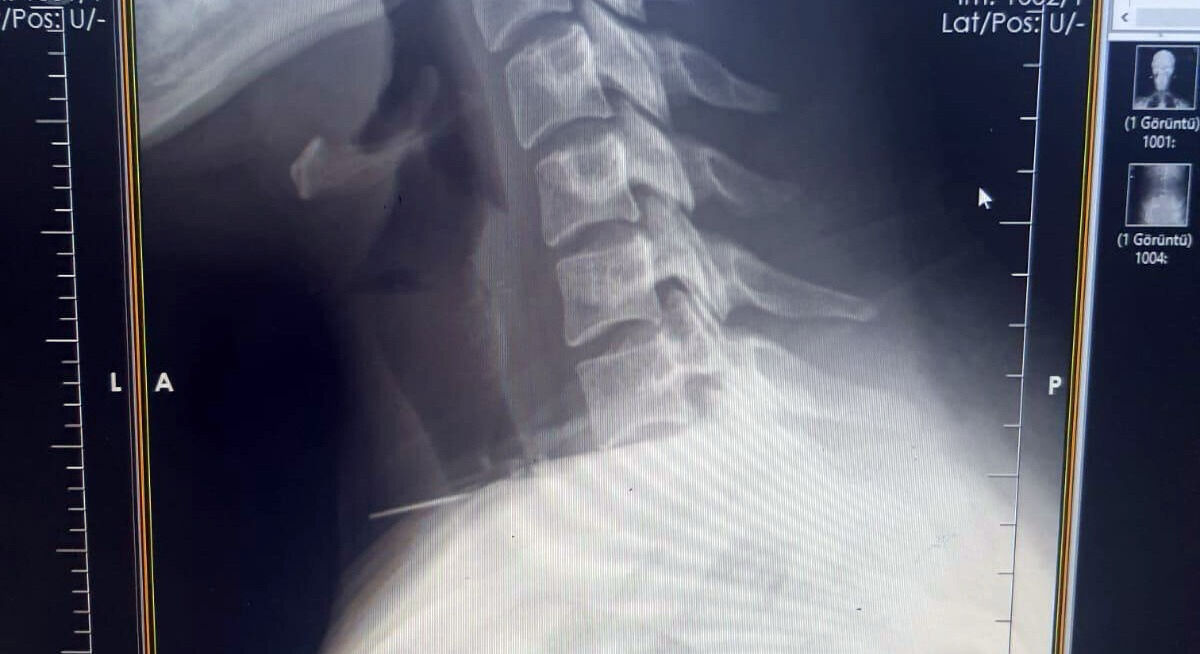

Radyolojik incelemeler ve klinik değerlendirmeler sonucunda, 3 santimetrelik iğnenin boğaz bölgesinin derinliklerine doğru ilerlediği tespit edildi. İğne, yaklaşık 1 saat süren ameliyatla çıkarıldı. Ameliyat sonrası süreci sorunsuz atlatan hasta taburcu edildi.